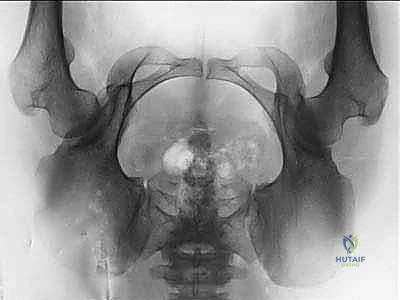

2. الأشعة السينية (X-rays): بأوضاع محددة لقياس زوايا التغطية (مثل زاوية CE وزاوية Tönnis) وتحديد درجة خلل التنسج.

بعد تحرير التجويف، يقوم الدكتور هطيف بتدويره في ثلاثة أبعاد (3D) ليغطي رأس عظمة الفخذ بشكل مثالي. يتم التحقق من التغطية الجديدة باستخدام جهاز الأشعة السينية الفلوروسكوبي داخل غرفة العمليات لضمان الزوايا المثالية.